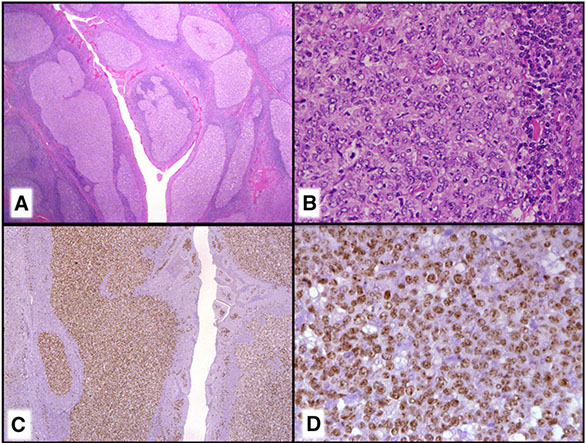

Cutaneous lymphoid hyperplasia in a 72-year-old man who presented with several purple-brown plaques on his cheeks and temples. A, The nodular infiltrate extends through the dermis with sparring of the overlying epidermis. B, It is characterized by scattered follicles with well-defined, reactive-appearing germinal centers, some of which have surrounding mantle zones. Many CD20-positive B cells are in the reactive follicles (C), and more numerous CD3-positive small T cells are present in the interfollicular areas (D). B-cell clonality studies (not shown) were negative for a clonal IGH or IGK gene rearrangement. [19]